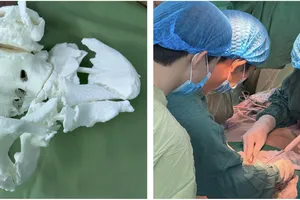

(SGGP). – Ngày 9-4, theo tin từ khoa Tai - Mũi - Họng BV Nhi đồng 1 TPHCM, các bác sĩ vừa tiến hành nội soi lấy ra một cây đinh dài 3,5cm, nằm lọt trong cuống phổi (phần phế quản gốc bên phải - ảnh) bệnh nhi M.H.N.T 6 tháng tuổi, ngụ Nha Trang - Khánh Hòa.

Bệnh nhi được chuyển khám tại BV tỉnh và phát hiện có cây đinh trong phổi nên tiếp tục chuyển lên BV Nhi đồng 1 TPHCM để lấy cây đinh ra.